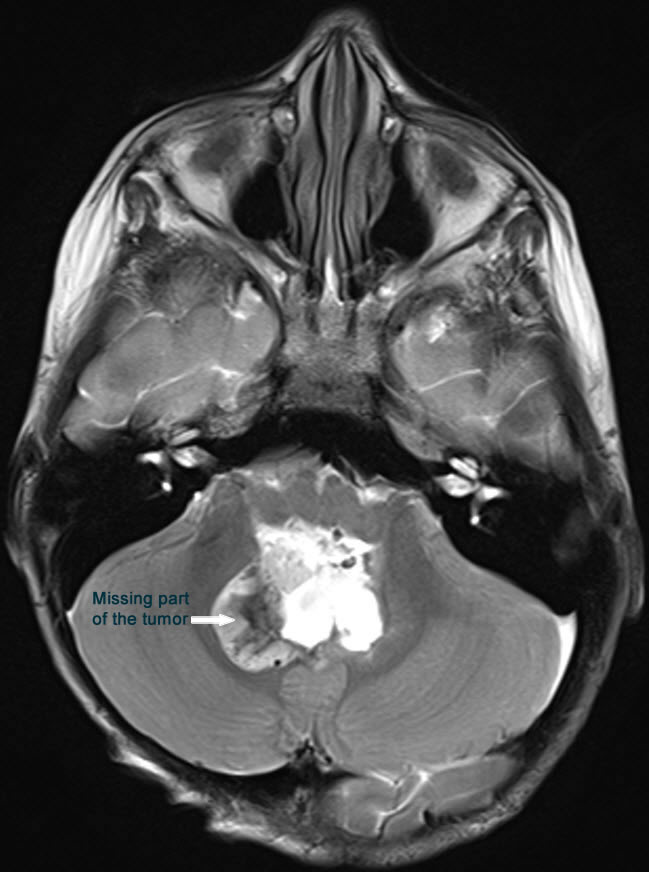

Midline posterior occipital approach in setting position. The bone flap reflected to the neck inferior. The dura was opened in V-shape fashion. The tonsils were shifted downward and the vermis is prominent by the tumor. Sharp dissection of the inferior pole of the vermis ( The uvula). The tumor was highly vascular with rich blood supply. The tumor was coagulated sucked and most of the upper part was removed. The inferior part was was removed until the  obex with related structures were seen. The left part of the tumor was followed and resected until the foramen of Leuschko was seen and the left inferior cerebellar peduncle was preserved. The same maneuver was undertaken in the right side. The tumor inside the 4th ventricle was removed and the floor of the 4th ventricle was seen intact with widened aqueduct through which the third ventricle was seen. The superior medullary velum was respected. The floor of the 4th ventricle was flattened due to the previous compression effect of the tumor, that it was impossible to see the median sulcus, nor the paramedian sulci limitantes or the hypoglossal trigone elevations at the calamis scriptorius. I got the impression that the tumor was totally resected, for what intraoperative MRI control with contrast was done. There is still part of the tumor in the right upper corner and the right foramen of Leuschko. Resection of this part was achieved until the normal cerebellar tissues were seen at these angles. Strict hemostasis with water-tight closure of the dura and bone flap was secured with 2 stitches and routine closure of the wound.

MRI done during surgery showing the missing part of the tumor, which was subsequently removed.